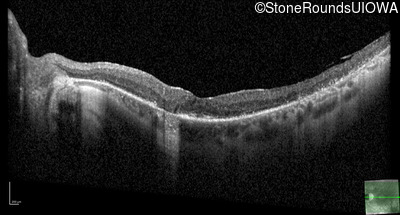

Optical Coherence Tomography - Left - 20/25 sc

Exemplar / OCT Stack

OCT Stack